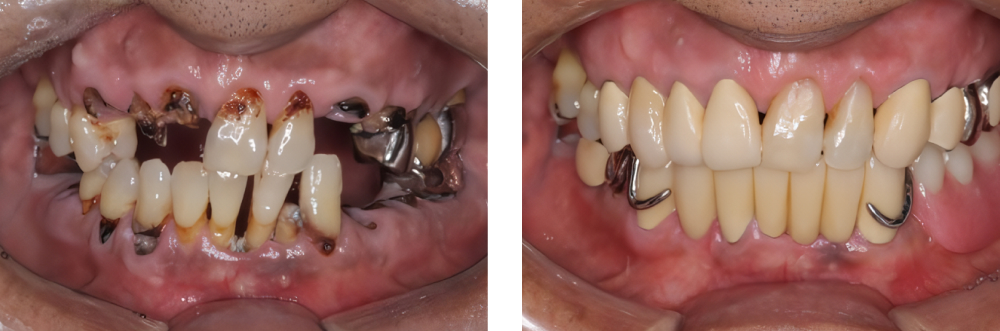

全顎保険治療

術前

術後

| 治療内容 | 全顎的に保険内で治療を行った |

|---|---|

| 治療期間・回数 | 約2.5年・約50回 |

| 費用 | 保険適用となります |

| 治療内容 | 全顎的に咬合再構成を行い保険内で治療を行った |

| 治療期間・回数 | 約4年・約50回 |